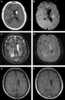

Hepatocellular carcinoma (HCC) is the most common type of primary liver cancer in adults and is currently the most common cause of death in people with cirrhosis.It occurs in the setting of chronic liver inflammation, and is most closely linked to chronic viral hepatitis infection (hepatitis B or C) or exposure to toxins such as alcohol, aflatoxin, or pyrrolizidine alkaloids. Certain diseases, such as hemochromatosis and alpha 1-antitrypsin deficiency, markedly increase the risk of developing HCC. Metabolic syndrome and NASH are also increasingly recognized as risk factors for HCC.As with any cancer, the treatment and prognosis of HCC vary depending on the specifics of tumor histology, size, how far the cancer has spread, and overall health. [Source: Wikipedia ]